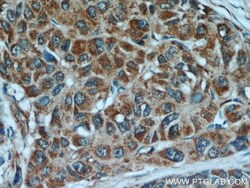

- Submitted by

- Invitrogen Antibodies (provider)

- Main image

- Experimental details

- Immunohistochemistry of paraffin-embedded human liver cancer using 14412-1-AP (PEG10 antibody) at dilution of 1:100 (under 40x lens).